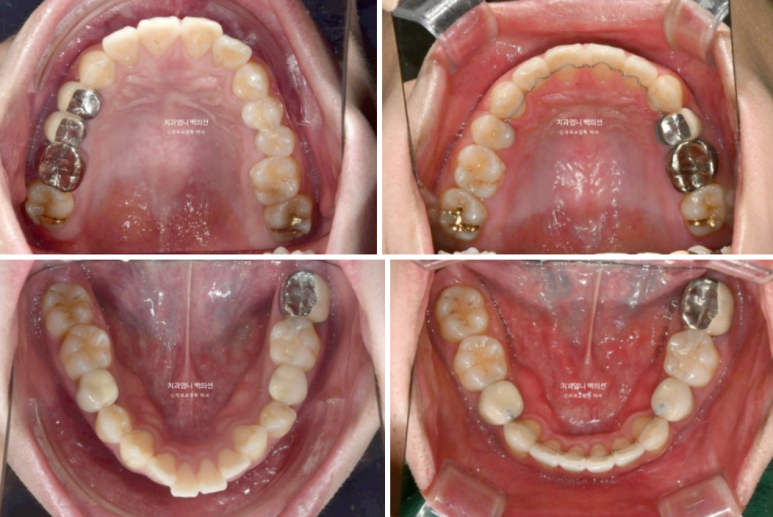

2022.12~2025.05

발치공간은 깔끔하게 마무리 되었습니다.

중심선과 캔팅의 개선

앞니 돌출의 개선과 적절한 앞니 각도

두번째 재제작으로 교합평면이 수평을 되찾았습니다.

뻗치지도 옥니도 아닌 적절한 앞니 각도